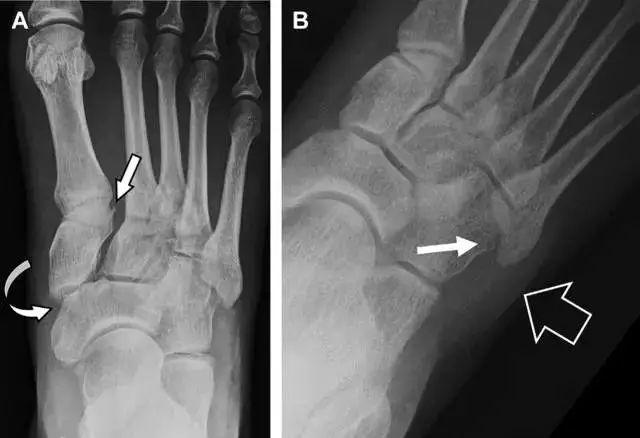

22跗跖关节复合体损伤

与跗跖关节韧带相关的骨折常由旋前或旋后的跖屈损伤引起。尽管跗跖关节骨折脱位仅占所有骨折的 0.2%,但是约 20% 的这些骨折在初次检查时被漏诊。初次 X 片可能示正常,但是负重位 X 线片常常提示脱位或半脱位。

典型表现:第二跖骨底和内侧楔骨之间的骨折碎片,跖骨间间隙增宽(图 8)。脱位亦可发生在舟骨-内侧楔骨关节,导致另一种变异的跗跖关节损伤(图 9A)。此外,骰骨的小块皮质撕脱在足部斜位片上可清晰显示(图 9B)。

图 8 从马上摔落的患者,跗跖关节骨折。A 正位片示内侧楔骨旁边的小骨折碎片(箭头),第二跖骨底向外半脱位;B 负重位侧位片示第二跖骨相对中间楔骨向背侧轻微移位(长方形);C STIR 序列 MRI 图像示跗跖关节韧带断裂(箭头),第一至第三跖骨、内侧楔骨及中间楔骨均骨髓水肿

图 9 变异的跗跖关节骨折。A  另一种类型的跗跖关节损伤,中间楔骨向内侧半脱位(弧形箭头),从而使第一、第二跖骨间间隙变宽,需注意,骨折在靠近内侧楔骨处(箭头);B 外侧跗跖关节损伤伴随从骰骨跖骨韧带的骰骨撕脱(箭头),需注意,第五跖骨底近端处存在软组织水肿(空箭头)